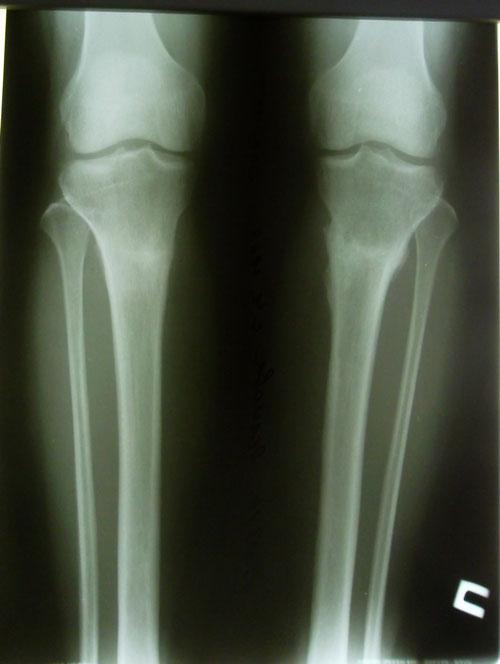

рентген в 76 дней.

Сращение отличное, предполагаемая дата снятия аппаратов - 06 января 2014г.

Рентген в 2 месяца после снятия аппаратов.

Разрешено всё без ограничений!